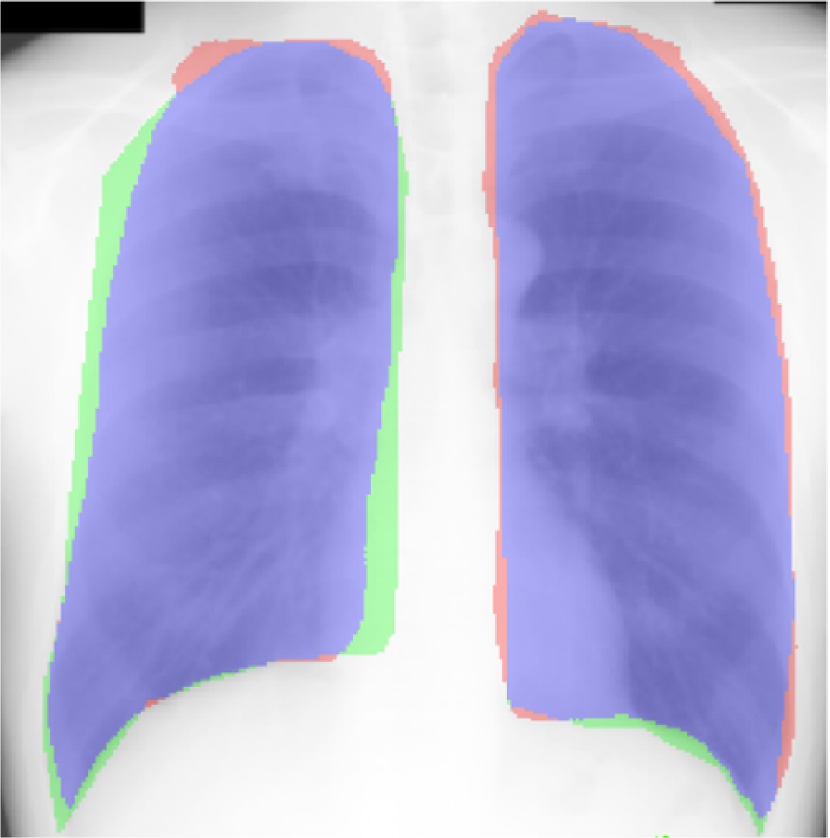

Fig. 9 presents the qualitative results of performing the lung segmentation using the proposed pipeline (ESL+MaShDL). The figure provides a visual insight on how inclusion of retro-cardiac region results in the segmentation label that is independent to the shape and structural changes in the close-by anatomical structures such as heart. For comparison purposes, similar qualitative results for the lung field labels obtained using the method proposed in [11] are provided in Fig. 10. As predicted before, the shape specificity is not preserved for the lung field labels obtained using [11]. This is further evident through the results presented in Table II. Moreover, unlike the proposed method, the U-net architecture uses an overlapping-based objective function (e.g., cross-entropy) which provides satisfactory results in cases with reduced shape variability. However, in the particular case of thoracic radiographs, the lung field labels without retro-cardiac space present higher shape variability than those observed when including this region. This could be a possible explanation of a slightly better overlapping-based performance (i.e., Overlap and DSC) by U-Net [11] when including the retro-cardiac space than without including it.

Traditionally, CAD algorithms designed to segment lung field from CXR ignore the retro-cardiac region, i.e., the lung region occluded by heart (Fig. 2(a)). The segmentation label without the retro-cardiac region provides only partial unobstructed lung field. Accurate delineation including the occluded retro-cardiac region, is necessary for correct diagnosis in diseases related to the change in lung capacity such as atelectasis (lung collapse), hyaline membrane disease, transient trochnpea, and Meconium aspirat. Fig. 2(c) presents the correlation between the lung volume estimated from computed tomography (CT) scans and the segmented lung field area from CXR (with and without retro-cardiac region) from 108 individuals. The plot shows a stronger overall correlation between the lung capacity calculated including the retro-cardiac region and the lung volume obtained through CT scans (R=0.80 without retro-cardiac region, R=0.86 including retro-cardiac region; no inspiration/ expiration information was available. R is the correlation coefficient).

Segmentation of the lung field including the occluded retro-cardiac region for reliable estimation of capacity and inter/intra subject comparisons.